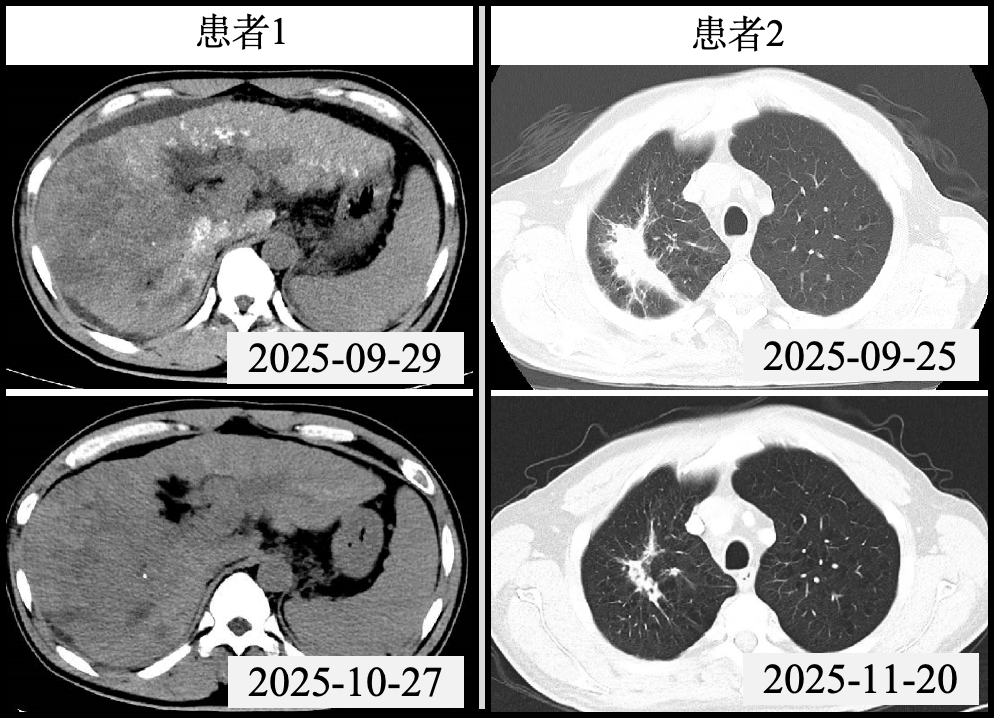

50岁的于某被确诊为“巨块型肝癌”,影像学检查显示其原发性肝癌已伴随门静脉主干、左右支、部分肝内属支、脾静脉及肠系膜上静脉起始处广泛癌栓形成,病情极为棘手。面对这一复杂病例,肿瘤综合介入病区MDT团队迅速响应,第一时间敲定序贯一体化治疗方案。治疗初期,肿瘤综合介入病区副主任王田蔚与副主任医师金星带领介入团队为患者实施经动脉化疗栓塞术(TACE),有效控制了局部病情进展。

针对广泛门脉癌栓这一治疗关键难点,肿瘤放射治疗专家于多副教授带领放射免疫团队精准施策,为患者量身定制局部精准放疗联合分子靶向治疗的综合方案,通过放射免疫协同实现对病灶的立体管控。在多学科团队的精诚协作下,患者治疗过程顺利且耐受性良好,复查结果显示肿瘤及癌栓均得到有效抑制,患者生活质量显著改善。

61岁的姜某因肺癌骨转移入院,且已继发腰2椎体病理性骨折,随时面临瘫痪风险。同时,胸部CT检查显示其右肺上叶存在占位,伴有肺门及纵隔淋巴结转移,病情危急且涉及多系统问题,亟需同步解决病理诊断、脊柱稳定和肿瘤治疗三大核心任务。

肿瘤综合介入病区的一体化诊疗模式再次发挥关键作用。王田蔚率先为患者施行CT引导下经皮腰2椎体穿刺活检术,明确肿瘤为肺部来源后,立即实施经皮穿刺椎体成形术,成功重塑脊柱稳定性,为后续肿瘤治疗筑牢基础。

随后,于多领衔的放疗团队制定了“全身-局部”协同治疗策略:先通过诱导化疗控制全身微小病灶,再开展同步放化疗。放疗计划精准覆盖胸部原发肿瘤及高危淋巴结引流区,同时对腰椎转移灶进行局部加量照射,实现“全身控制”与“局部根治”的有机统一。目前,患者疼痛症状显著缓解,活动能力基本恢复,肺部及腰椎病灶明显缩小,治疗成效获得患者及家属的高度认可。